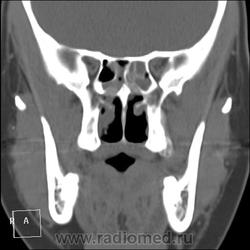

КТ ППН и носоглотки. Девушка 21 года. Полипозный риносинусит.

Госпитализирована для оперативного лечения. Удалены полипы носа. Вторым этапом планируется гайморотомия. Во время операции - подозрение на образование носоглотки. Сохраняется затруднение носового дыхания. Направлена на КТ. Категорически отказалась от контрастировния (лекарственная полиаллергия, боится).

Полип в носоглотке справа. Нарушена пневматизация придаточных пазух носа кроме левой решётчатой. В левой гайморовой на дне неясно что…

На дне гайморовой - полип, в носоглотке немаленький хоанальный полип. Там всё в полипах, а они и фиброзные бывают, и ангиофибромы, и ангиоаденомы... Вот и плотность разная.

На операции визуально полипы аденоматозного типа. Какие будут гистологически после гайморотомии - сейчас трудно сказать. Если б гиперденсность была только по нижней стенке верхнечелюстной пазухи, тогда вариант с аспергиллезом на пломбировочном материале, на мой взгляд, был бы более вероятен. У девушки участки гиперденсности по всем стенкам верхнечелюстных пазух, в основной пазухе, совсем чуть - в решетчатом лабиринте слева, без костной деструкции. Без посева и гистологии - только гадать)). В носовой полости признаков грибкового поражения ЛОРы не отмечают. Но Вы правы, может иметь место изолированное поражение синусов.